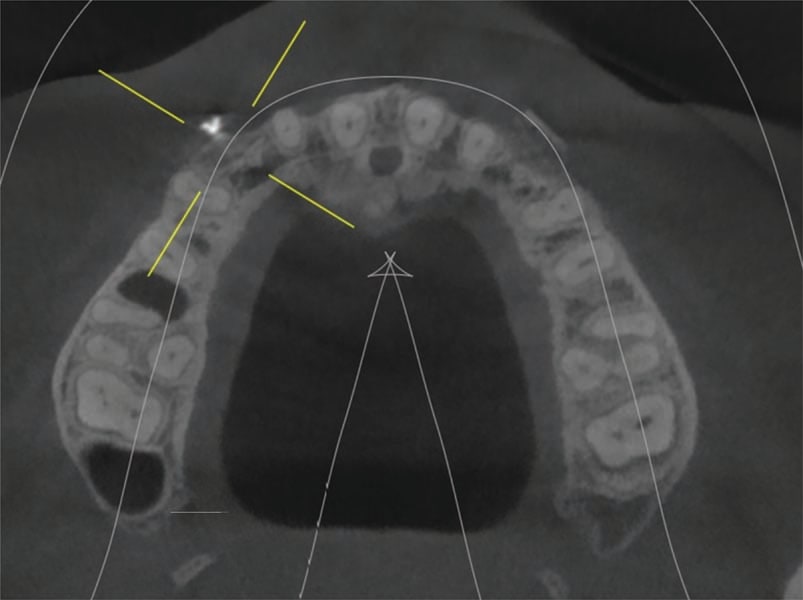

The oral surgeon, Dr. Defalco, saw the patient, and a CBCT was taken. Cross-sectional views at 6 and 11 noted a narrow ridge width due to a concavity at both sites related to lack of the permanent canines (Figure 5). Minimal roots were present for the deciduous canines (teeth C and I). Insufficient ridge width was present at either site to permit implant placement without site grafting to eliminate the facial ridge concavity. Block grafting of the sites at the time of extraction was recommended, and following site healing and graft conversion to the host ridges implants could be placed.

The grafts were allowed to heal for 6 months (Figure 10 through Figure 12). A CBCT was taken to evaluate the ridge width at the grafted sites. Analysis determined adequate ridge width was now present to allow implant placement. The patient presented to Dr. Puccio and Dr. Defalco for placement at sites 6 and 11. Consent forms were reviewed with the patient and signed. Local anesthetic was administered and a full thickness flap elevated to expose the fixation screw on the facial aspect of the ridge that had been placed to secure the block grafts. The screw was removed from both sites. A surgical guide (fabricated in a similar fashion as discussed above) was inserted intraorally, and osteotomies were created after fixation screws were removed at sites 6 and 11. A 3.6-by-11-mm EV Profile implant (Astra Tech) was placed at each site. Cover screws were placed and the flap secured with sutures. The patient returned at 2 weeks post implant placement. Healing appeared uneventful, and the patient was scheduled for a recall prophy.

At 3 months post implant placement the patient returned to initiate restoration of the implants. A CBCT was taken to check bone levels on the integrated implants. Panoramic and occlusal views were analyzed verifying the implants in contact with the surrounding bone and appeared ready to restore (Figure 13 and Figure 14). Local anesthetic was administered, and the implants were uncovered with the Solea CO2 laser and the healing screws exposed (Figure 15). Healing abutments were placed in the implants and the patient scheduled for impressions.